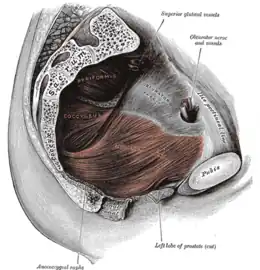

Structures entourant la hanche droite. Les muscles du bassin.

Les muscles du bassin. Les artères de la région fessière et fémorale postérieure.

traverse la grande incisure ischiatique qu'il partage en deux espaces : supra-piriforme et sous-piriforme.

Le muscle piriforme fait partie des muscles qui ferment l'enceinte du bassin pour séparer les viscères pelviens de la racine des membres inférieurs.

Le muscle piriforme est un repère très important dans la région fessière. En traversant la grande incisure ischiatique, il la divise en une partie inférieure et une partie supérieure, déterminant ainsi la terminologie supérieure (au-dessus du muscle) et inférieure (en dessous du muscle) pour les nerfs et vaisseaux de la région.